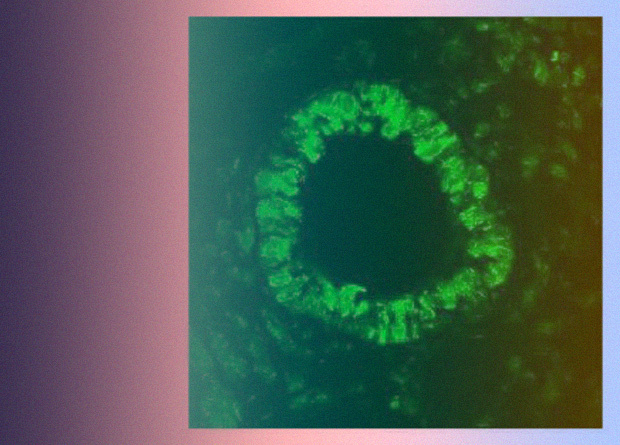

С помощью полимеразной цепной реакции ученые подтвердили наличие мРНК FFA4 в легком мыши в степени, существенно превышающей наблюдаемую для второго родственного рецептора жирных кислот FFA1. Иммуногистохимический анализ показал, что FFA4 экспрессируется преимущественно в клетках эпителия средних и нижних дыхательных путей.